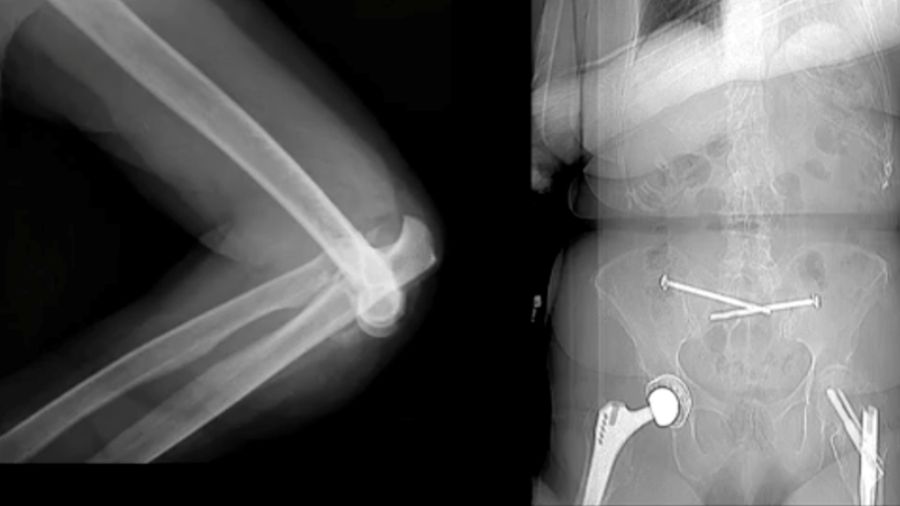

Case 5: 46-year-old male, athlete

A 46-year-old athlete with a comminuted coronoid fracture and severely damaged radial head required multiple surgeries after an overstuffed radial head prosthesis caused complications. The final solution was a total elbow prosthesis, underscoring the importance of careful prosthesis sizing and ligament repair.